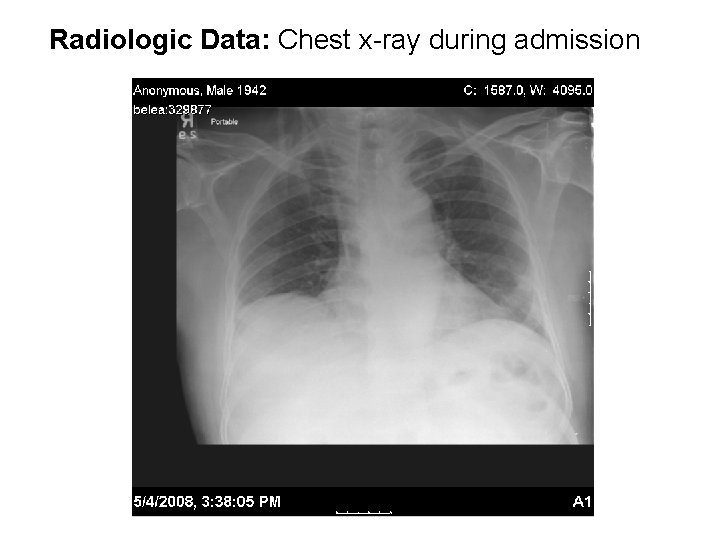

Radiologic Data: Chest x-ray during admission